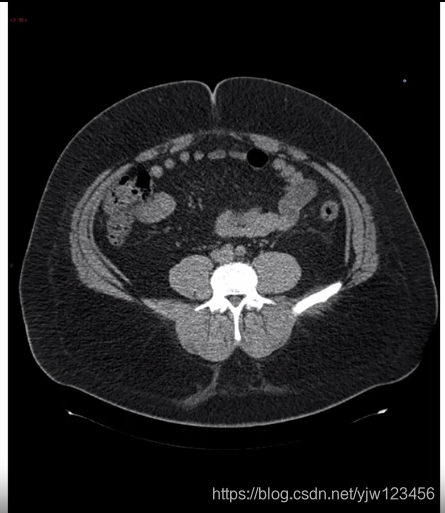

那3维数据是怎样的呢,假设接受CT扫描,它可以得到你身体的三维模型的X光扫描。

可以得到人体躯干的不同切面

所以3维数据通常除了高度和宽度外还有一个深度:

注意3维图像中还是会有一个通道数的,这里假设是黑白图片,所以通道数为1。